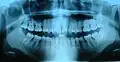

Ортопантомограмма зубов